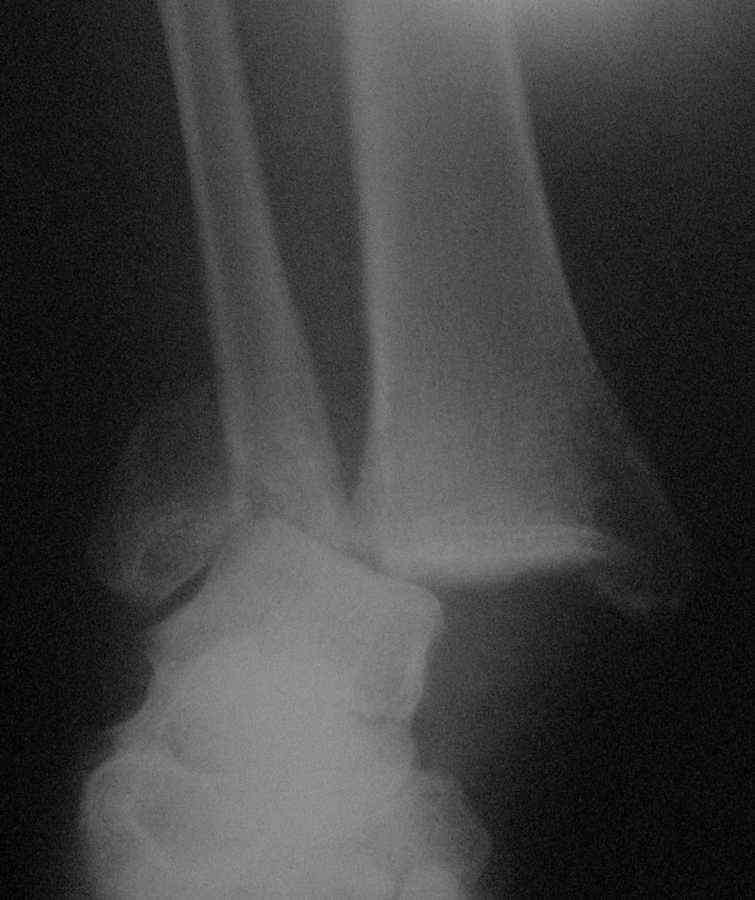

Застарелый перелом наружной лодыжки, разрыв дельтовидной связки, задне-наружный вывих стопы. |

Сегодня, 19.11.09. поступила больная 37 лет с представленной рентгеновской картиной. Анамнез травмы и заболевания следующий: 2.10.09 больная была направлена в приёмный покой с Дз: закрытый перелом наружной лодыжки со смещением отломков. Больной при поступлении выполнена закрытая репозиция, гипсовая иммобилизация U-образной лонгетой, госпитализирована. На следующие сутки больная самовольно покинула отделение. Со слов больной - лечилась дома самостоятельно, 15.11.09 вызвала хирурга на дом в связи с неприятным запахом из под гипса, на дому хирург снял гипс, были отмечены нагноившиеся пролежни циркулярно по задне-наружному краю стопы. Гипс был снят, проводилось местное лечение хирургом на дому. Больная не пользовалась костылями, наступала на травмированную конечность. После заживления ран направлена хирургом с Диагнозом: двухлодыжечный перелом правой голени. Дополнения к анамнезу: посттравматическая энцефалопатия, органическое заболевание головного мозга, хронический гепатит "С". Ожирение. Предложены следующие тактики лечения: 1. низведение стопы аппаратом. 2. артродезирование с использованием аутотрансплантата,металлофиксация. 3 длительная гипсовая иммобилизация. Либо одномоментное артродезирование с использованием БИОС( ЭОПа нет и не будет, Гвоздь....б\у) Просим высказать ваше мнения и предложения.

1) Вторую бы проекцию посмотреть.

извините, вот вторая проекция